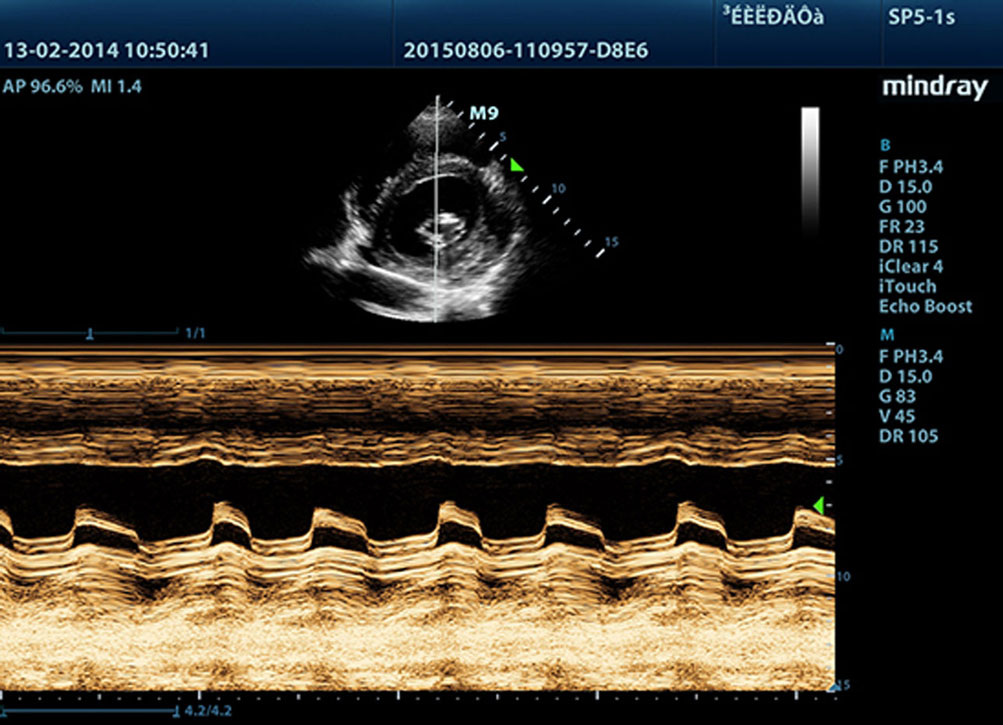

Free Xros M?

?? ???? ?? ??? ???? ???? ??? ???? ??? ??? ? ????. ?? 3?? ?? ??? ??? ???? ?? ?? ??? ??? ? ????.

Free Xros CM?

??? ??? ??? ???? ???? ???? ??? ??? ???? ??? ? ????. ?? ?? ??? ?? ??? ??? ?? ? ????.